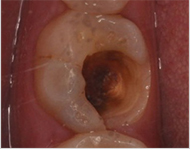

深圳博愛曙光口腔專家表示:採取補牙術是為了阻止齲齒繼續惡化。所謂補牙就是採用用人造物質修補牙體缺損的方法,用於修補的物質叫充填材料。凡因齲齒、楔狀缺損、外傷等造成牙體組織缺損者都需要修補,以恢復其外形和功能。

除净病变组织,保护牙髓和健康牙齿组织,建立良好的固位形和抗形,以免造成继发龋。

早龋,一次消毒即可进行补牙,中龋或深龋,则需m三至五次,如果涉及到牙神经则需根管治疗。